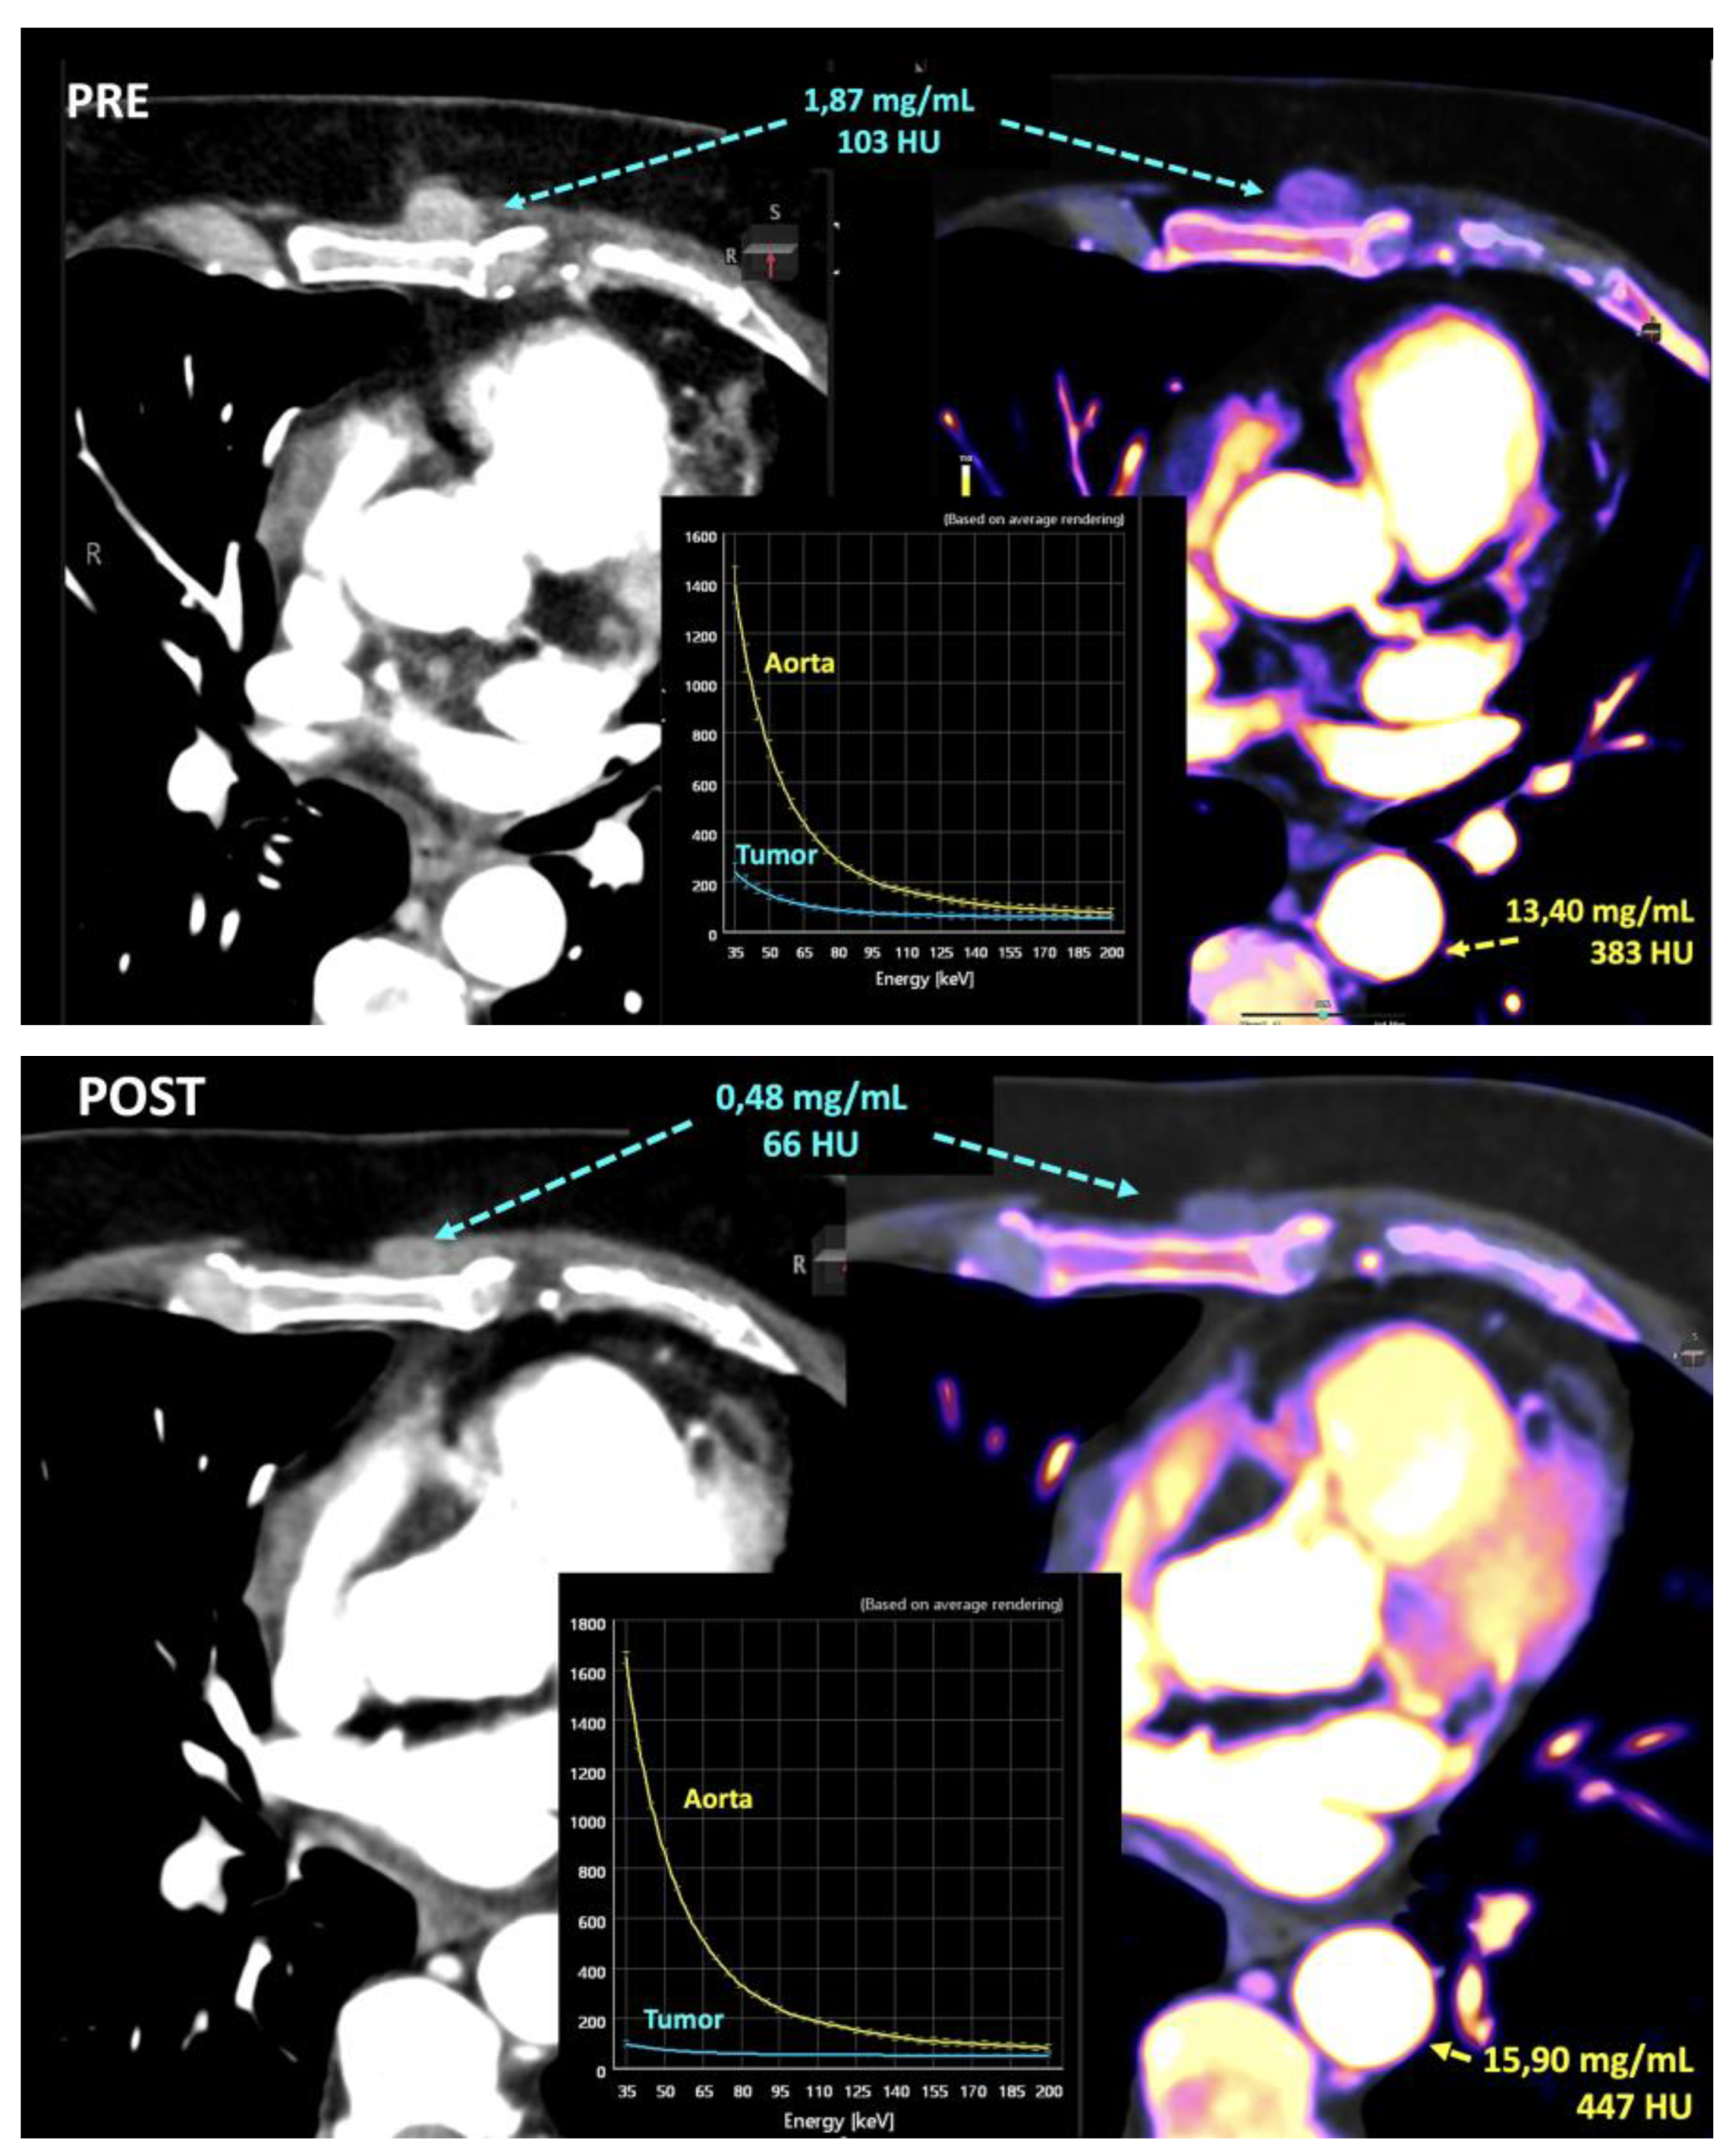

- Iodine concentration may be a surrogate marker of changes in tumor perfusion due to therapy [79]. Different iodine-related parameters have been proposed such as concentration of intralesional iodine, vital iodine tumor burden, and (lesion volume × iodine concentration) may be more sensitive than the evaluation criteria based on maximum diameter or change of CT value.

- Zeff is also a quantitative index for characterization of composition of a voxel, although a biological correlation of these changes to tumor microenvironment is challenging.